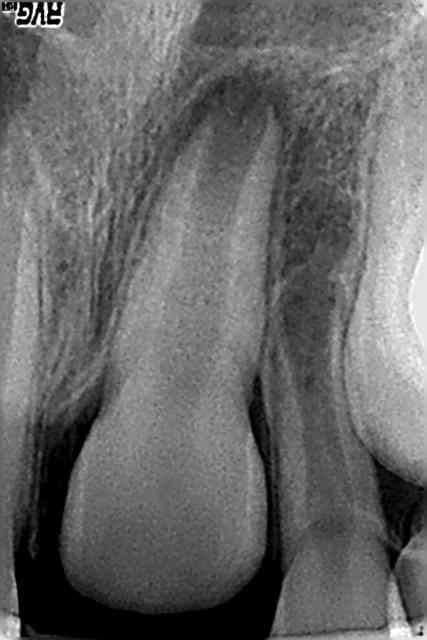

Voici un cas clinique de pédodontie:

Enfant de 4 ans et 7 mois.

Découverte fortuite lors du brossage par ses parents. Pas de douleurs signalées par l'enfant. Pas de souvenir de traumatisme pas de témoins mais l'enfant est un peu "cascadeur". Enfant en bonne santé générale.

Sur la radio, on observe une image de résorption latérale.

Pas de douleurs à la palpation ou au contact dentaire de la 51. Mobilité peut être un peu supérieure à la mobilité physiologique entre le pouce et l'index mais difficile a évaluer.

Quel est votre diagnostic? Quel traitement mettriez vous en place? quel est votre pronostic?